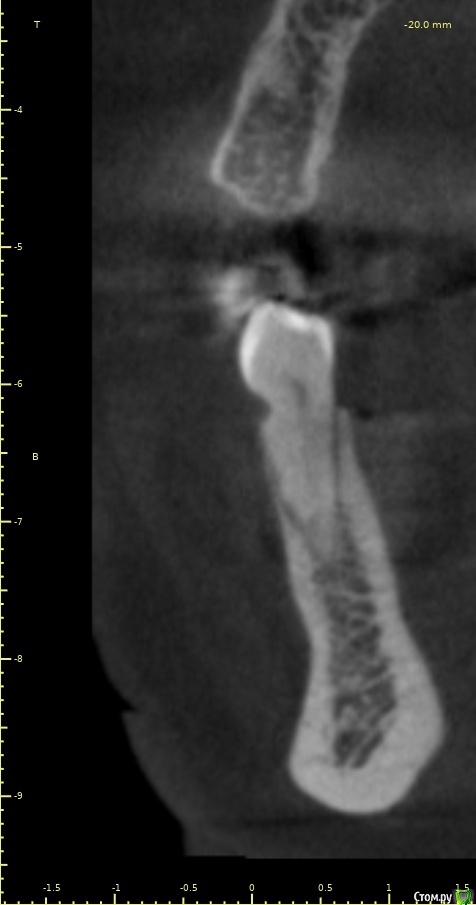

Женька Опубликовано 14 декабря, 2020 Автор Поделиться Опубликовано 14 декабря, 2020 (изменено) Наконец-то получил КТ от пациентки...Боли значительно уменьшились, практически не беспокоит... Коллеги, что думаете? Я так понимаю это уже не фон от титана? и вердикт всё-таки один? Сам склоняюсь всё-таки более к понаблюдать. Вестибулярно конечно очень тонко Толщина была ~ 6.7мм Изменено 14 декабря, 2020 пользователем Женька Ссылка на комментарий

Irouil Опубликовано 14 декабря, 2020 Поделиться Опубликовано 14 декабря, 2020 Ну и где тут язычно передавленная кортикалка? Меня смущает только картина в области верхушки симптомного винта, ну и заглубление Я бы дождался уже срока интеграции Ссылка на комментарий

Женька Опубликовано 14 декабря, 2020 Автор Поделиться Опубликовано 14 декабря, 2020 Ну и где тут язычно передавленная кортикалка? Меня смущает только картина в области верхушки симптомного винта, ну и заглублениеНе знаю, я про язычную кортику не говорил. Меня тоже смущает... и в области соседа такого фона (а это не фон я уверен) нет... А с заглублением что не так? по прицелам там 1.5-2мм, на кт почему-то этих мм вообще нет и как будто крестально стоят Ссылка на комментарий